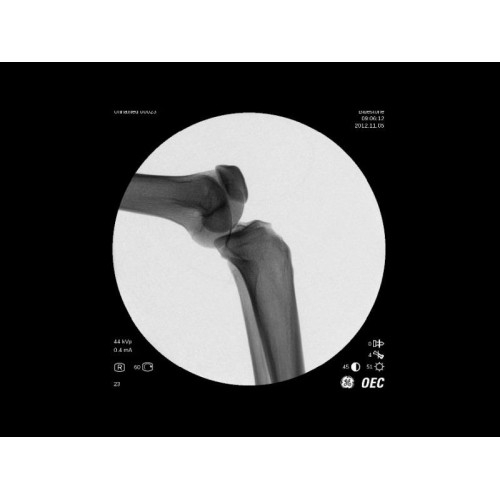

- Ортопедические операции

В практической работе GE Brivo OEC 785/865 демонстрирует стабильно высокое качество визуализации, что особенно важно при проведении сложных малоинвазивных вмешательств. Оборудование позволяет сократить время процедуры и повысить ее безопасность для пациента. Многие хирурги отмечают удобство работы с системой и ее надежность в интенсивной эксплуатации.